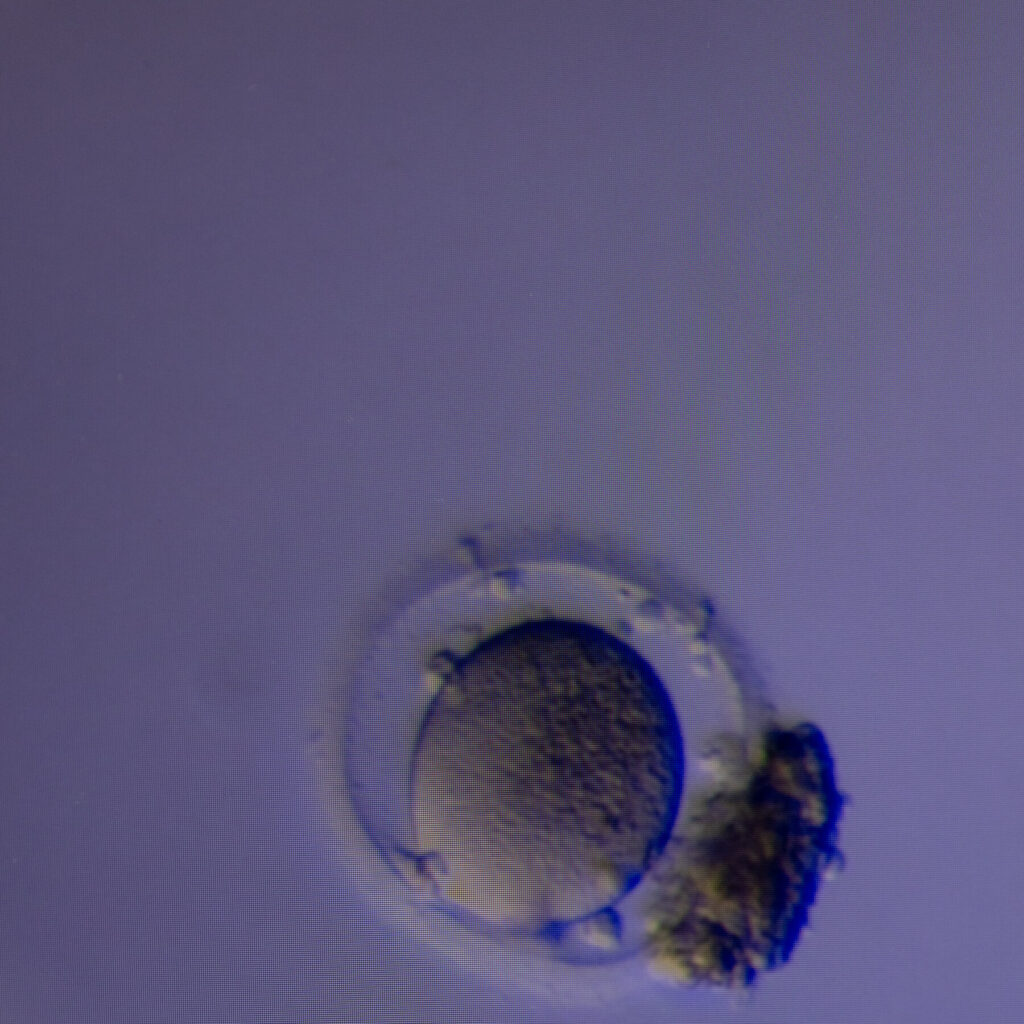

New Method Can Find Hidden Eggs to Aid in Fertility Treatment

A study reported that the conventional method of searching follicular fluid didn’t find all the eggs. The new technology found extra eggs more than half the time.A study reported that the conventional method of searching follicular fluid didn’t find all the eggs. The new technology found extra eggs more than half the time. Read More